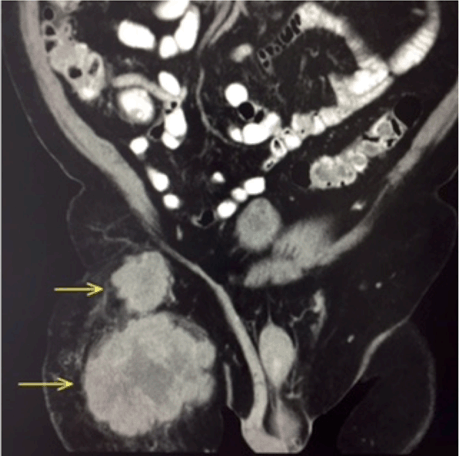

All routine hematological and biochemical parameters were normal. Serologic tumor markers (CEA, lactate dehydrogenase, alpha-fetoprotein, prostate-specific antigen, human chorionic gonadotropin, CA125, and CA19-9) were within normal limits. An abdominal CT scan with contrast revealed two inhomogeneous masses anterior to the right rectus femoris (proximal 3.4x4.8 and 6.3x10.7; (Figure 2)) suggestive of enlarged lymph nodes. Chest CT and colonoscopy were normal.

Figure 2: Coronal abdominal computed tomography scan of the abdomen at presentation showing two inhomogeneous masses in the right groin (yellow arrows).